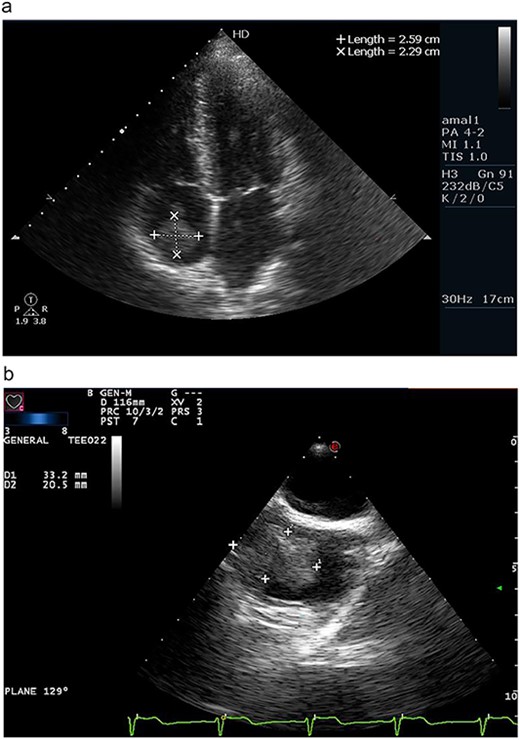

Transthoracic echocardiography demonstrated an irregular right atrial mass attached to the atrial wall with wide base near the atrial connection with the inferior vena cava (IVC) causing partial IVC dilation without significant flow obstruction. In addition, there was a mild tricuspid regurgitation and systolic pulmonary pressure measured 47mmhg (Fig. 1a).

(a) Apical four chamber view on transthoracic echocardiography revealing a right atrial mass measuring 2.59 × 2.29 cm. (b) Transesophageal echocardiography confirming the presence of wide-based, irregular and lobulated right atrial mass measuring 3.32 × 2.05 cm.